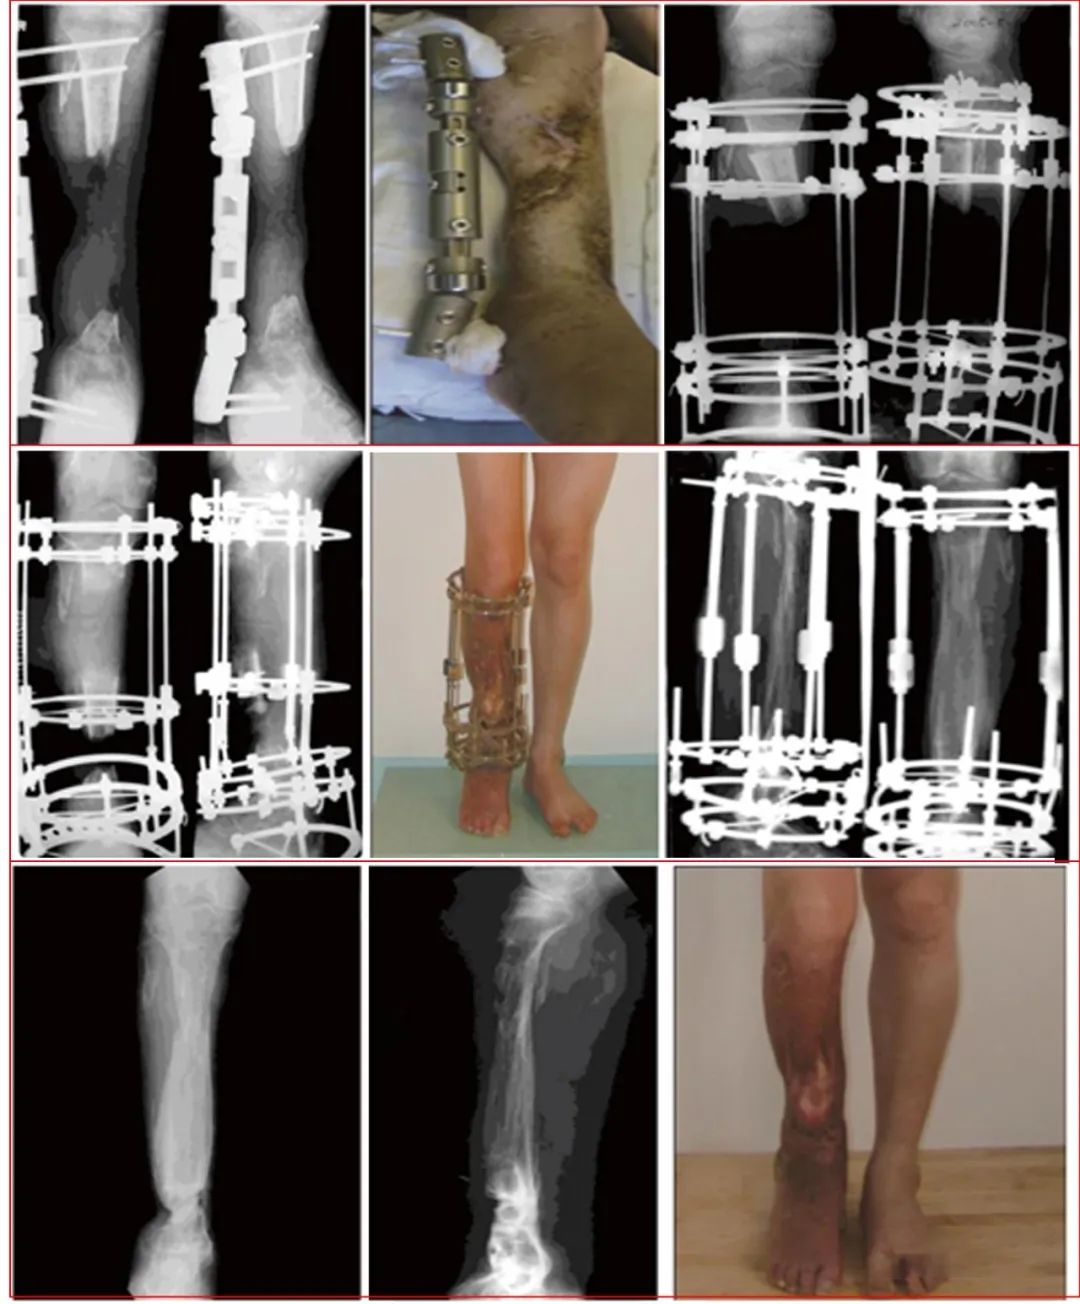

病例一 男,34岁,因火器伤致右小腿开放性粉碎性骨折,在当地医院应用带锁髓内针固定,创面皮肤感染坏死,髓内针外露。病灶清除后留有20cm长的胫骨缺损和6×12cm皮肤缺损。应用骨段与皮肤延长及加压固定和创面换药等综合外科措施治疗。创面肉芽新鲜后,应用皮肤牵伸术逐步修复创面;

病例二 患者,男,23岁,患者主因“右小腿外伤术15个月余”入院。患者11月前车祸致右小腿开放骨折,多次手术清创,胫腓骨缺损约18cm,胫前肌群和腓骨肌群缺损。诊断:①右胫腓骨骨缺损;②右胫腓骨延长术后。治疗周期约两年,拆除外固定。